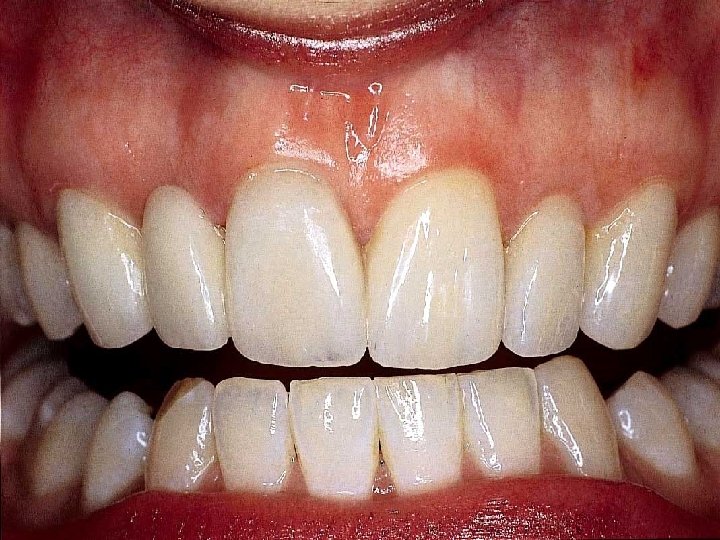

All Ceramic Crown Preparation Design & Function Shoulder marginal integrity structural durability periodontal preservation resistance Axial Reduction retention and resistance structural durability Rounded Line Angles structural durability

All Ceramic Crown Preparation Design & Function Shoulder marginal integrity structural durability periodontal preservation resistance Concave Cingulum Reduction Axial Reduction structural durability retention and resistance structural durability Rounded Line Angles structural durability

All Ceramic Crown Preparation Design & Function Shoulder marginal integrity structural durability periodontal preservation resistance Vertical Lingual Wall retention and resistance Concave Cingulum Reduction Axial Reduction structural durability retention and resistance structural durability Rounded Line Angles structural durability

Cementation Procedure 1. Remove temporary and all residue of temporary cement 2. Check occlusion on adjacent teeth (mylar shimstock and articulating paper) 3. Place rubber dam 4. Clean tooth with pumice and rubber cup, rinse and lightly dry 5. Try in restoration for fit.

6. Adjust proximal contacts if necessary 7. Evaluate shade intraorally using water soluble try-in paste (optional) 8. Rinse out try-in paste and air dry 9. Etch inside of restoration (HF porcelain etchant X 2 minutes), rinse with distilled water and air dry 10. Place drop of silane (porcelain primer) on intaglio surface for 1 minute, lightly air thin to evaporate solvent